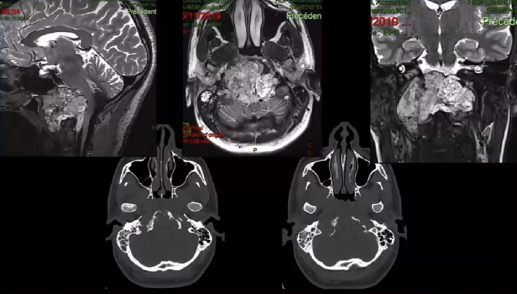

▼下图所示案例肿瘤看着很大,然后用30度、45度甚至70度的内镜,我们有很多带角度的器械,利用这些器械就可以切除肿瘤。可以先切开黏膜,然后把蝶窦内的黏膜推开,然后进入肿瘤。目前我们正在努力的开发这方面的器械,没有这些器械我们是做不了手术的。

▼下面就是我所说的有角度的器械,然后我们用脂肪来修补,我们在内镜下做缝合,在内镜下做缝合很复杂难度很大,所以很花时间,但是它是值得的。

▼这是术后的MRI,大家看到的高信号的是脂肪组织,我觉得利用内镜到达颅颈交界区更简单。

▼这是一个较大肿瘤的案例,它严重影响到枕髁,我们用神经内镜,通过抽吸可以切除大部分,然后和显微镜配合。

▼这是术后的MRI